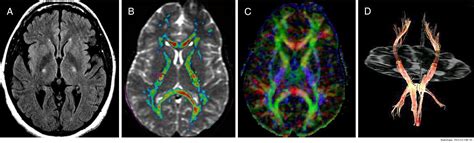

• Imaging Studies: Magnetic Resonance Imaging (MRI) or Computed Tomography (CT) scans may be used to rule out other possible causes of symptoms, such as tumors or spinal cord compression.